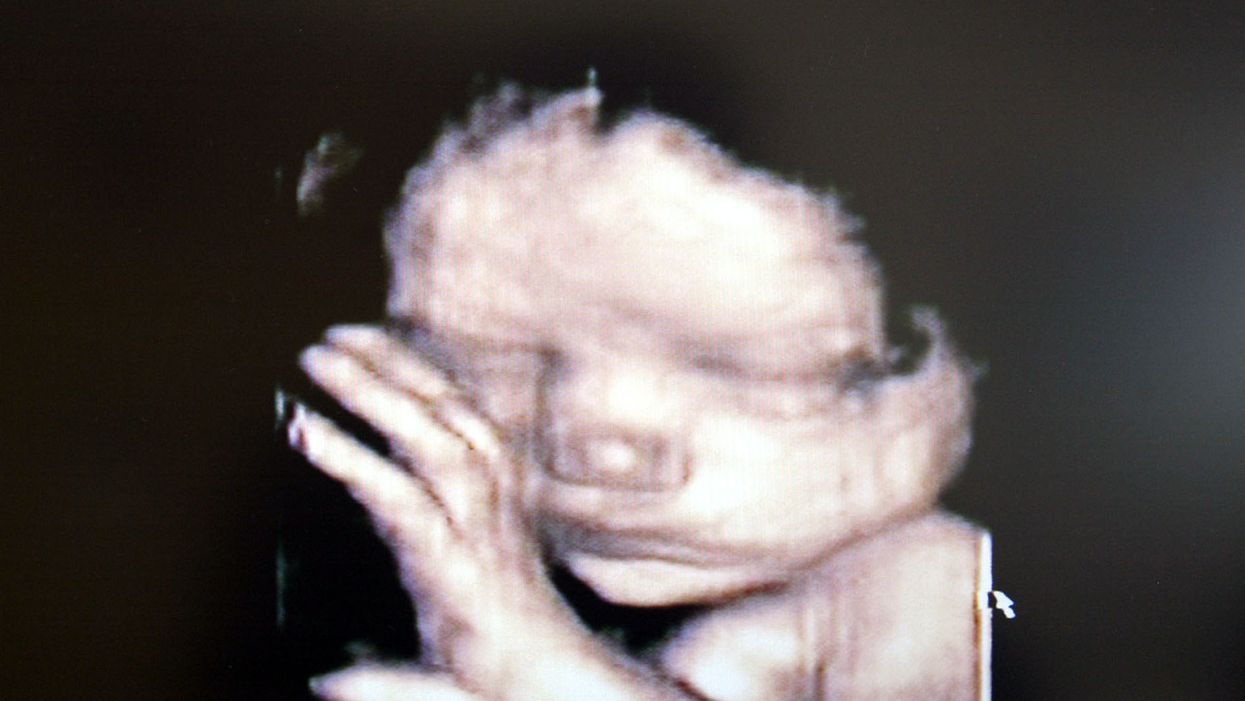

Photo by Fotopress/Getty Images

Scatton, a Christian who would have turned 18 last week, discovered she was pregnant when she was 17 years old. Months after she discovered she was pregnant, she received news that she had an inoperable brain tumor.

Her options weren't good: She could either begin radiation treatment to possibly prolong her life, negatively impacting the growth of her unborn child, or she could opt to avoid treatment until the baby was born. Scatton's daughter, Aries, was born at 33 weeks in January.